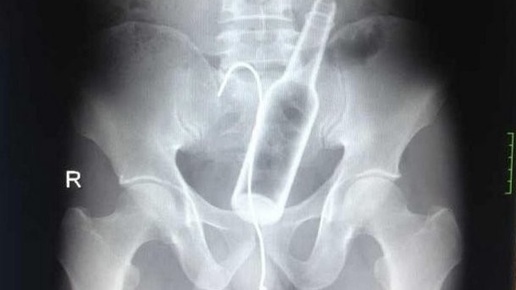

30 находок внутри человеческого тела: от ложек до магнитов

Человеческое тело — загадка, способная удивить даже опытных врачей. Иногда люди проглатывают или вставляют предметы, которые кажутся немыслимыми: от столовых приборов до живых существ. Мы собрали 30 невероятных случаев, когда в желудках, кишечниках и других органах находили странные объекты. Эти истории заставят вас то смеяться, то содрогаться! Причины варьируются: случайность, психические расстройства, любопытство, попытки контрабанды или даже ритуалы. Дети часто проглатывают мелкие предметы из любопытства, взрослые — из-за невнимательности или эксцентричных привычек...